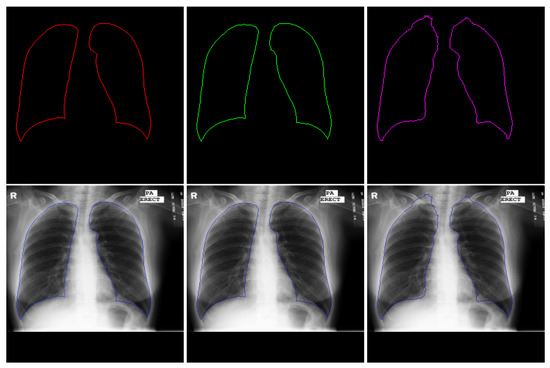

4.2.2. Lung Segmentation

- We propose to append the customized SISR trunk with multiple computing heads to learn different visual tasks in medical images. We evaluate our approach using CXR datasets to generate HR representation followed by jointly performing lung segmentation (visual task 1) and abnormality classification (visual task 2). We focus mainly on these two tasks because classification and segmentation are the key tasks in most medical image analysis applications.

| Model | Accuracy | Loss | IoU |

|---|---|---|---|

| Baseline (HR) | 0.9863 | 0.0355 | 0.9464 |

| Baseline (scale 2) | 0.9700 | 0.0545 | 0.9263 |

| Hydra Head (scale 2) | 0.9858 | 0.0316 | 0.9516 |

| Baseline (scale 3) | 0.9613 | 0.0496 | 0.9285 |

| Hydra Head (scale 3) | 0.9897 | 0.0248 | 0.9599 |

| Baseline (scale 4) | 0.9390 | 0.0557 | 0.9201 |

| Hydra’s Head (scale 4) | 0.9801 | 0.0325 | 0.9229 |

| Baseline (scale 8) | 0.9516 | 0.0816 | 0.8839 |

| Hydra Head (scale 8) | 0.9830 | 0.0411 | 0.9391 |